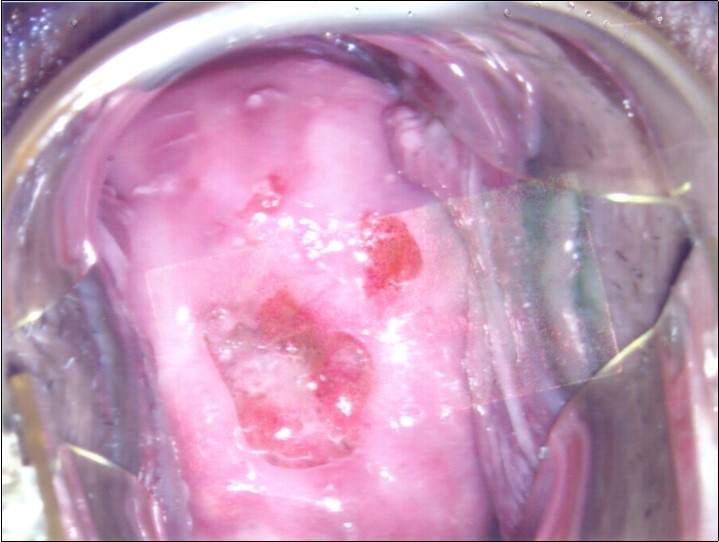

Repeat colposcopy was performed after 6 weeks. This revealed a small ulcerated area at the site of previous biopsy with rolled healing edges, and a separate small ulcer at the 12 o’clock position. (Figure 2a, Figure 2b, Figure 2c) Careful inspection of the buccal mucosa revealed similar ulcers in the left buccal region. (Figure 3)

Figure 2a.Repeat colposcopy (low magnification)

Figure 2b.Repeat colposcopy (high magnification)

Figure 2c.Repeat colposcopy (high magnification)